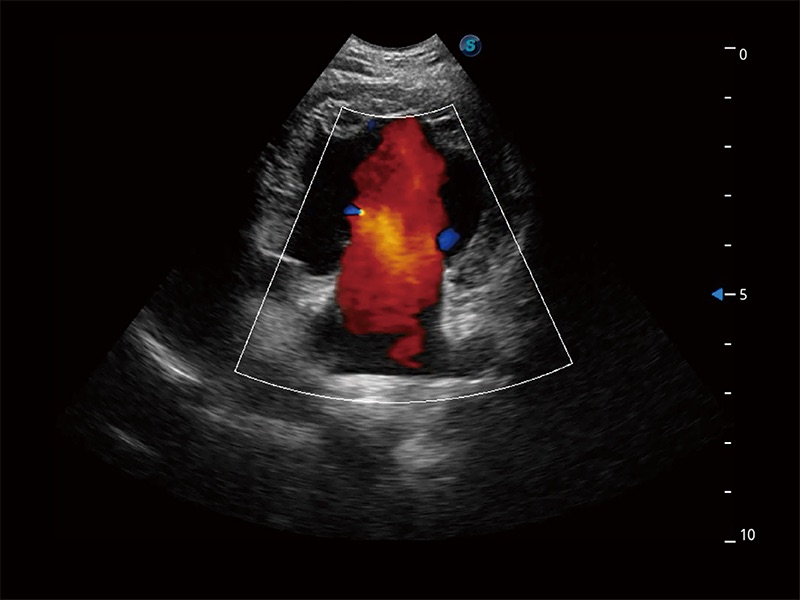

极大提升超低速微细血流的检出能力,同时更精准地滤除软组织和超声信号,为兽用医生提供以往无法通过常规血流获得的疾病诊断信息。

非线性融合造影成像充分利用谐波和基波信号,为难以观察的血流进行增强显像。可用于线阵、凸阵、微凸阵、相控阵探头。